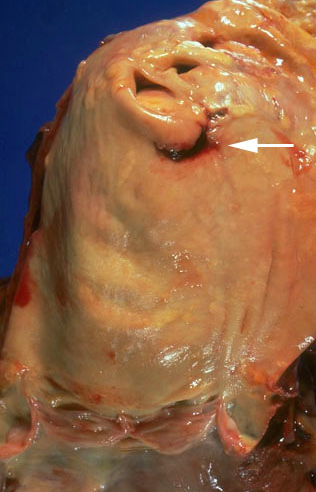

- Previous extensive transmural MI involving the free wall of the left ventricle. Note that the thickness of the myocardial wall is normal superiorly, but inferiorly is only a thin fibrous wall

- Infarction was so extensive that, after healing, the ventricular wall replaced by thin band of collagen, forming an aneurysm. Such an aneurysm represents non-contractile tissue that reduces stroke volume and strains the remaining myocardium. Stasis of blood in aneurysm predisposes to mural thrombosis.